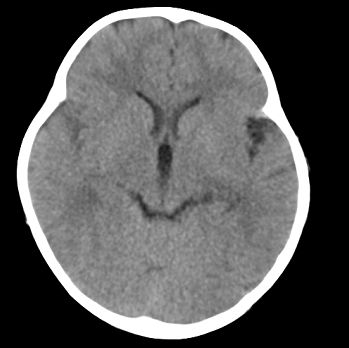

以下是引用22222222在2008-6-9 21:03:00的发言:[br]病灶周围见脑组织包绕,上部可见等或稍高密度壁环绕,壁且见小点钙化-----考虑皮样囊肿或表皮样囊肿可能,但侧脑室颞角内病灶不排除.